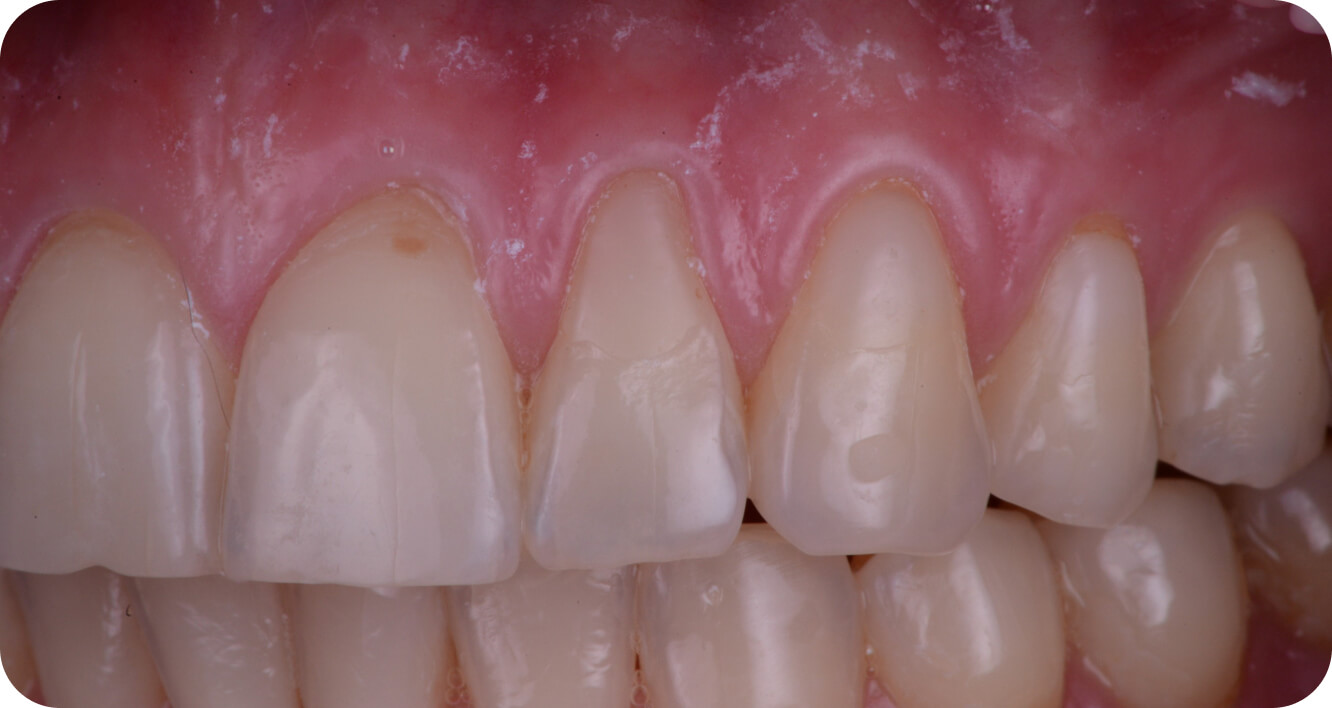

Мои работы

до/после

Большие

работы